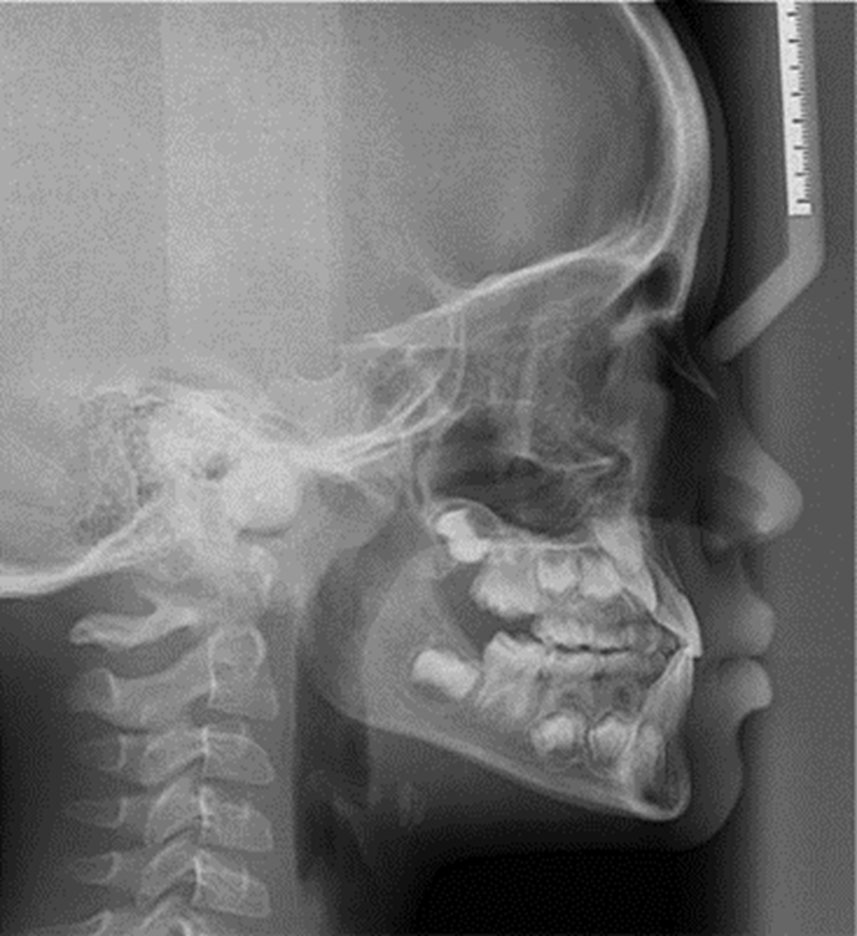

Autor: María Gabriela Flores Bracho. Fuente: Historia Clínica de M. C. M. H. 6 años. 04- 2010

Figura 6. Radiografía de perfil o lateral.

Autor: María Gabriela Flores Bracho. Fuente: Historia Clínica de M. C. M. H. 6 años. 04- 2010. Paciente con aparato encapsulado cementado en boca, fijado con acrílico en el sector del tornillo para inmovilizarlo después de la expansión rápida. Se observa diastemas en zona central que nos muestra la separación de la sutura media pos ERM y mejora en la relación de overjet.